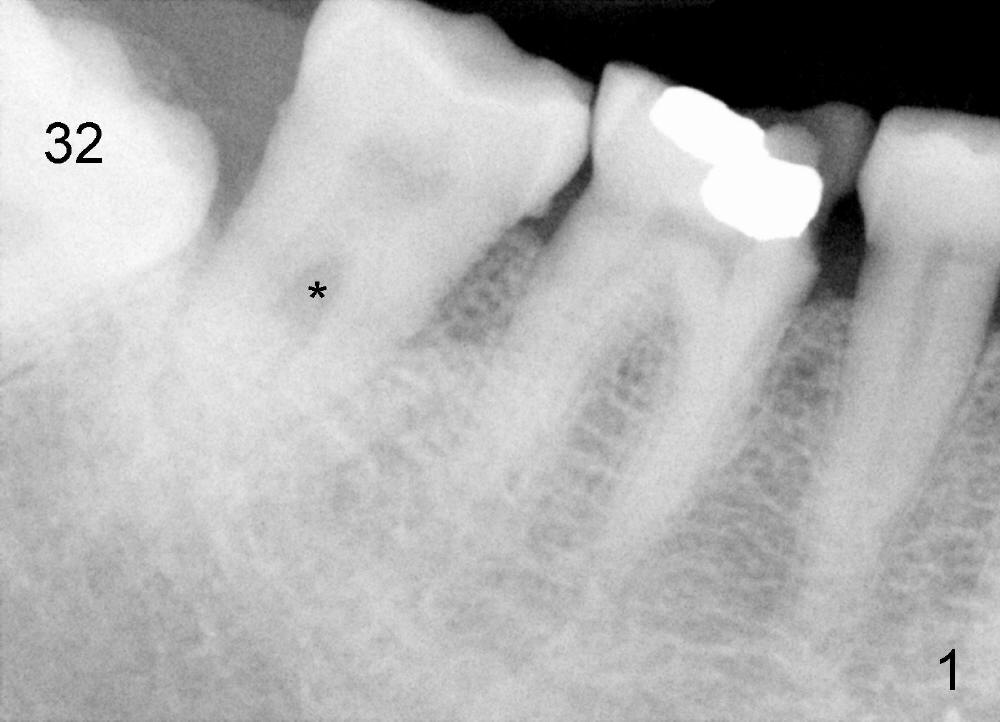

Mrs. Hwang in her sixties has had periodontal disease in her lower right 2nd molar (Fig.1 *). Three years later, both the 2nd and 3rd molars are extracted (Fig.2; pink: the upper border of the inferior alveolar canal). Four months after extraction, the patient returns for implant placement at the site of #31 (Fig.3, 4). The socket of the 2nd molar is outlined in yellow in Fig.3.